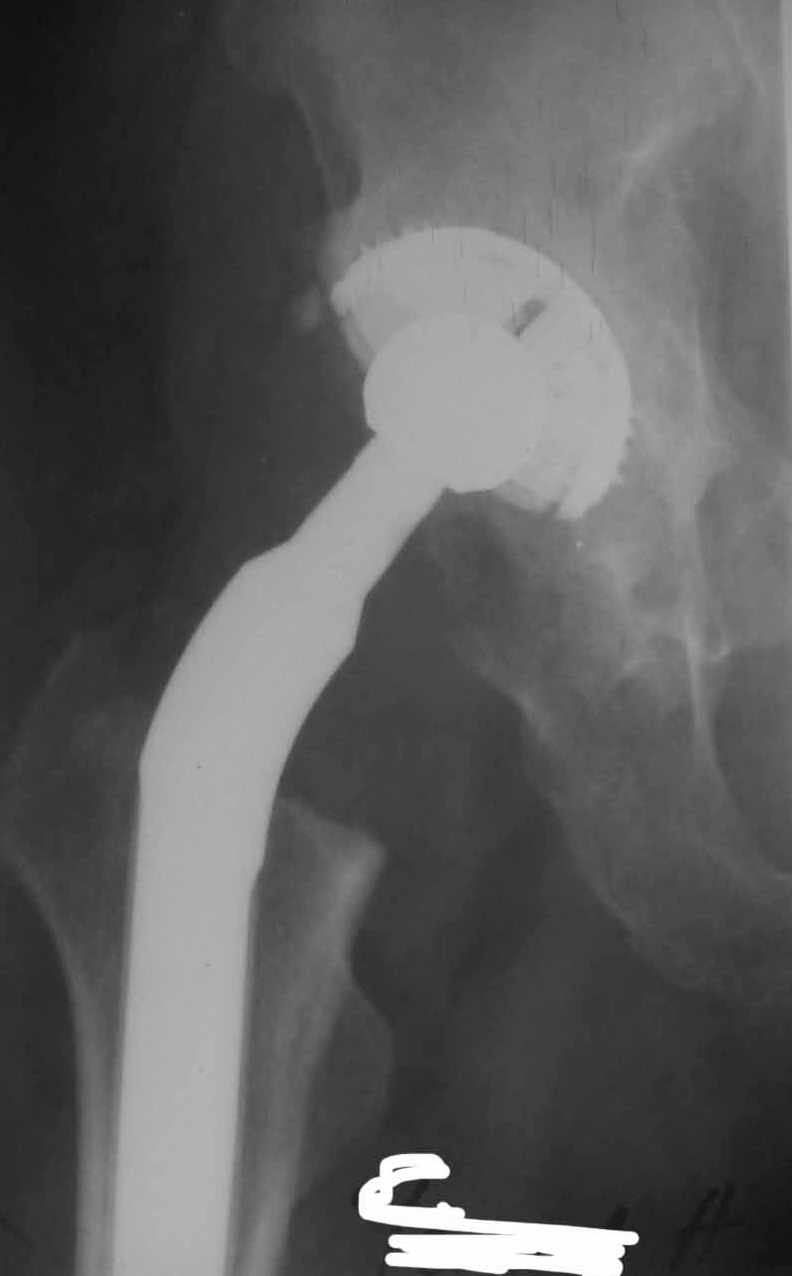

Re: вывих головки эндопротеза

Консультировать вывихи по рентгенограммам, не зная хода операции, дело не очень благодарное. Я думаю, что с датой операции Вы ошиблись и это был 2004 год? Тем не менее. Настораживают два фактора. Первое - не видно большого вертела. Если с мышцами обошлись грубо и их отсекли, то это очень грустно и нужна "связанная" пара, т.н. "constrain cup". Смущает хорошо прослеживаемый малый вертел и небольшая ретроверсия чашки. Возможно это (избыточная ретроверсия ножки и чашки) могло послужить причиной вывиха. Обычно гипсовая повязка после операции не накладывается, значит, были глубокие сомнения у оперировавшего хирурга. В этом случае - ревизия с перестановкой как минимум - ножки, а как максимум - обоих компонентов.

Во вложении - рентгенограммы после вывиха и после вправления.